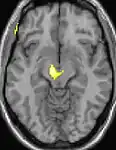

Positron emission tomography (PET) scans indicate the brain areas which are activated during attack only, compared to pain free periods. These pictures show brain areas that are active during pain in yellow/orange color (called "pain matrix"). The area in the center (in all three views) is specifically activated during CH only. The bottom row voxel-based morphometry (VBM) shows structural brain differences between individuals with and without CH; only a portion of the hypothalamus is different.[33]

| Positron emission tomography (PET) shows brain areas being activated during pain | ||

| Voxel-based morphometry (VBM) shows brain area structural differences | ||